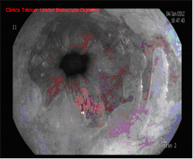

Radiofrequency with HALO system

The HALO radiofrequency ablation system safely and uniformly ablates the oesophageal mucosa to a depth of approximately 1 mm. Ablation is a technique in which tissue is heated until it is no longer viable or alive. HALO technology is a very specific type of ablation where heat energy is applied precisely and in a controlled manner. Clinical trials have demonstrated that Barrett's tissue can be completely eliminated with HALO ablation technology in 98.4% of patients.

Endoscopic follow-up is required, and treatment generally needs to be repeated in one or two sessions.